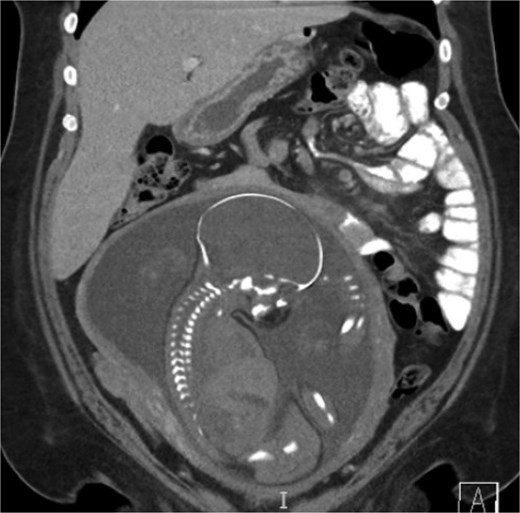

A 38-year-old female (Gravida 5, Para 2) at 30 weeks and 1 day gestation with history of a LRYGB performed to treat gastroparesis in the setting of morbid obesity presented to the Emergency Department with acute-onset severe epigastric pain exacerbated by eating. She reported associated nausea and diarrhea, and denied emesis, heartburn, fever, constipation, or dysuria. She was hemodynamically normal with normal fetal heart tones and laboratory results. She underwent esophagogastroduodenoscopy, which revealed a normal-appearing gastric pouch and jejunal mucosa, without evidence of a marginal ulcer. Abdominopelvic CT imaging demonstrated mesenteric swirling with clustering of small intestines entirely on the left abdomen suspicious for IH (Figs 1 and 2). Fluoroscopic small bowel follow through did not demonstrate evidence of small intestinal obstruction. On hospital Day 9, she remained unable to tolerate oral intake, and after multidisciplinary discussion with providers and the patient, she was scheduled for surgical repair.

Coronal CT demonstrating left upper quadrant mesenteric swirling with cluster of small intestine entirely on the left abdomen.